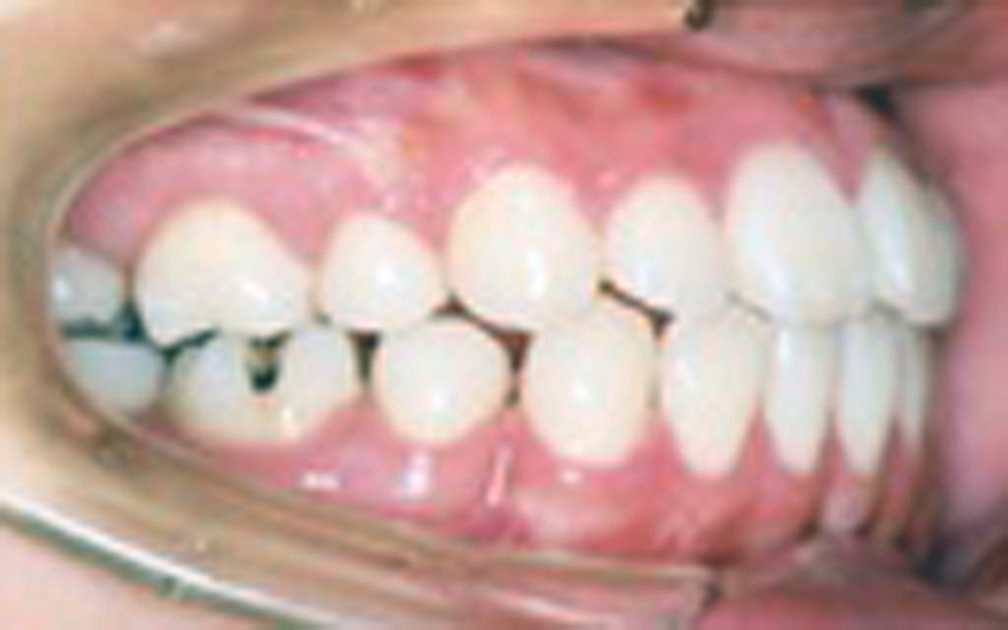

矯正の症例1 (診断名)上顎前突(ジョウガクゼントツ)